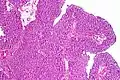

| Histopathology of transitional carcinoma of the urinary bladder. Transurethral biopsy. Hematoxylin and eosin stain. | |

Transitional cell carcinoma, also called urothelial carcinoma, is a type of cancer that typically occurs in the urinary system. It is the most common type of bladder cancer and cancer of the ureter, urethra, and urachus. Symptoms of urothelial carcinoma in the bladder include hematuria (blood in the urine). Diagnosis includes urine analysis and imaging of the urinary tract (cystoscopy). Transitional cell carcinomas arise from the transitional epithelium, a tissue lining the inner surface of these hollow organs.[1] When the term "urothelial" is used, it specifically refers to a carcinoma of the urothelium, meaning a transitional cell carcinomas of the urinary system.